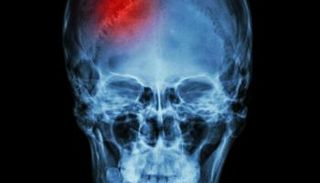

علاج جديد يحمي مرضى السكتة الدماغية من الموت أو الشلل.. ما تفاصيله؟